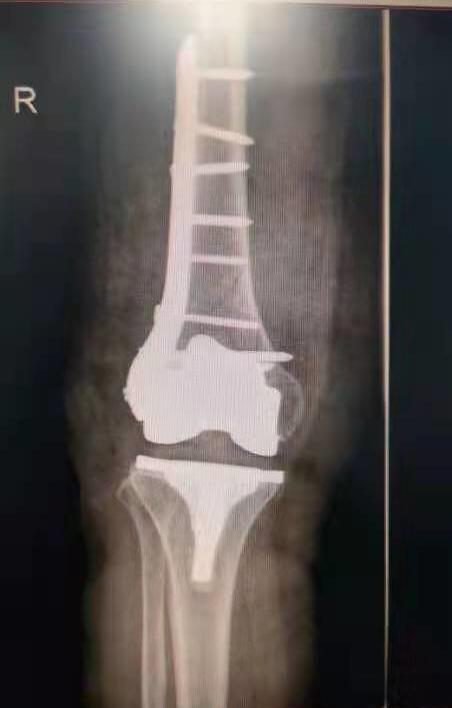

手術(shù)后照片